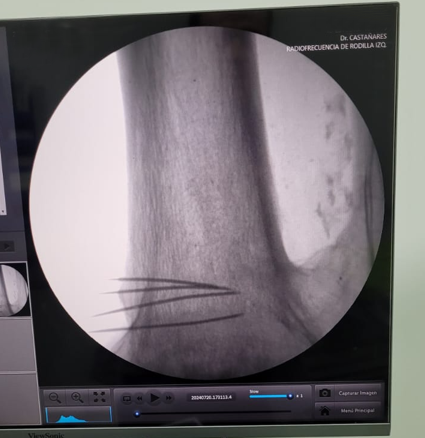

En Tidol tratamos el caso de un paciente de 90 años, con artrosis severa de rodilla izquierda.

El paciente presentaba limitaciones de reemplazo total de rodilla y no se le podía realizar la cirugía por osteoporosis y comorbilidad; por lo que se decidió realizar tratamiento con radiofrecuencia de los nervios geniculados.

Previo al tratamiento, el paciente no podía caminar debido a dolor; luego del tratamiento mejoró notablemente su sintomatología, comenzando a realizar la rehabilitación con fisioterapia dirigida.